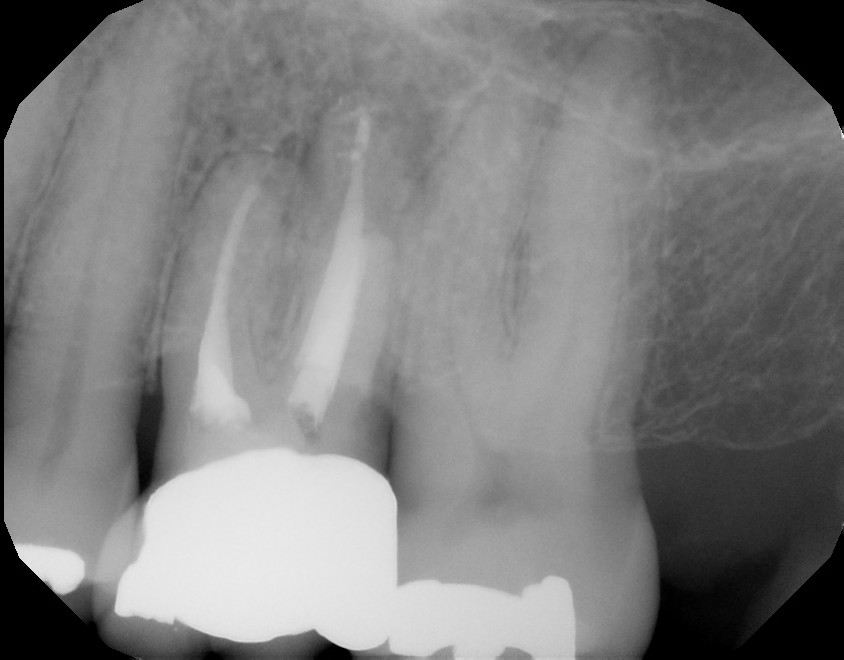

Surgical PreOp